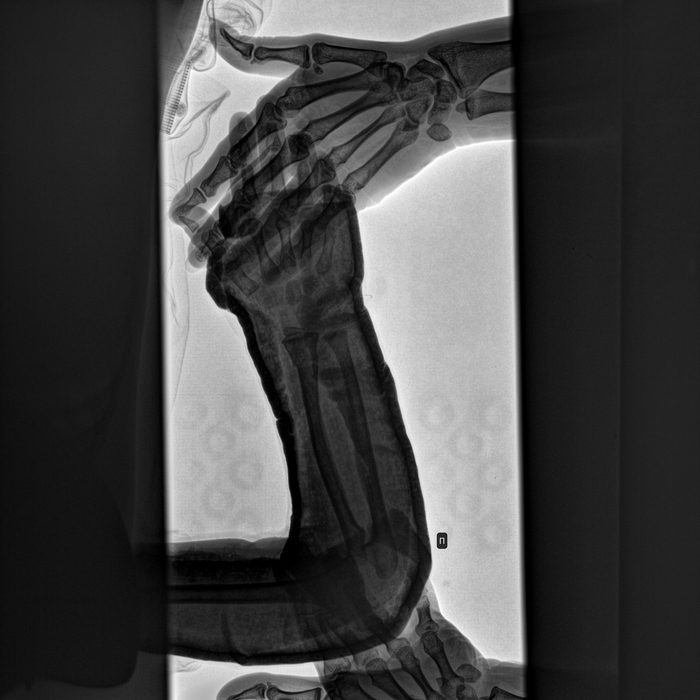

Здравствуйте. В постах о работе было много ортопедов, надеюсь на Вашу помощь. Кратко ситуация: ребенок 3.8 года сломал кость предплечья (перелом со смещением) 29.05.23г. Сделали операцию, неделя в стационаре, выписка, более 3х недель дома в гипсе, при снятии гипса (в больнице по месту житества, т.е. не там, где делали операцию) врач сообщил, что сомневается, правильно ли срослась кость (на всех предыдущих рентгенах сомнений у врачей не было). Другой врач тоже сомневается и намекает, что наверное нужно ставить спицу. Поймите правильно, лишний раз оперировать ребенка это большой стресс и делать этого не хочется без 100% необходимости.

Прикладываю последний снимок в котором сомневаются от 28.06.23 (делали при снятии гипса), другие снимки и выписной эпикриз из стационара.

Сейчас ребенок рукой двигает, пользуется полностью. Болей и прочих неудобств нет.